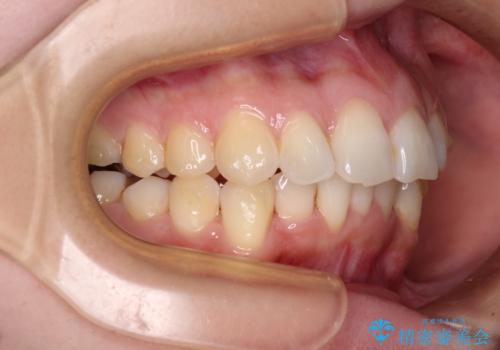

- 前歯のデコボコで前方に出ていることを気にして来院された患者様です。

上顎前歯が捻れて前方に飛び出しており、下顎前歯もそれに沿うようにデコボコとなっていました。

IPR(歯と歯の間を削る処置)によりスペースを獲得して上下顎前歯のデコボコを改善し、飛び出している前歯が引っ込むように設定し、インビザラインにて矯正治療を行うこととしました。